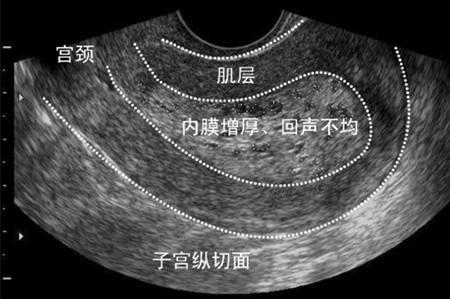

子宫内膜增厚,这在我们生活中是非常常见的一种情况。因为有许多女性会出现子宫内膜增厚。子宫内膜增厚有什么危害呢?有以下几个方面:

子宫内膜的增厚与女性体内的激素水平有关,子宫内膜的增生主要是由于内分泌失调所导致,容易导致女性脸上长斑和皮肤暗黄。

卵巢周期中产生卵子分泌雌孕激素导致子宫内膜的血运增强,导致子宫内膜增厚,增生期内膜,有可能影响到女性的怀孕。